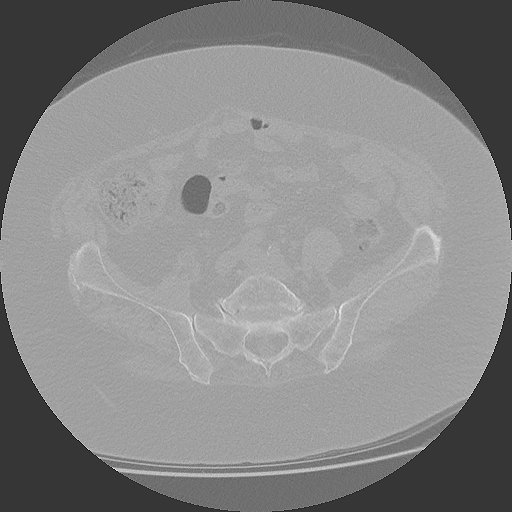

04.03.2025

CT Becken mit Radiologiebefund

DICOM PDF

Aktuelles CT des Beckens mit schriftlichem Befund.

CT Becken

853 Bilder in 4 Serien | 86 MB

4 Serien verfügbar

März 2025

CT Becken + Überweisung

CT-Untersuchung mit Befund, Überweisung zur weiteren Behandlung